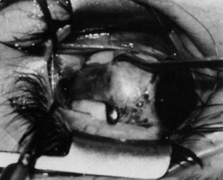

Step 8. The two layers of intermuscular septum on the toe of the Stevens hook are opened anterior to the tendon with a blunt Westcott scissors, as shown in Figure 14A. A second Stevens hook is passed through the anterior opening in intermuscular septum and beneath the tendon from anterior to posterior. These two Stevens hooks, passing beneath the tendon in opposite directions, securely hold the tendon in place until the tenotomy is completed. The tenotomy is performed between them with blunt Westcott scissors, as shown in Figure 14B, with care taken not to damage adjacent intermuscular septum. The opposite pointing Stevens hooks hold the tendon securely until it is completely transected and the hooks are released.

Fig. 14. A. The two layers of intermuscular septum on the toe of the Stevens hook are opened anterior to the tendon with blunt Westcott scissors. B. A second Stevens hook is passed through the anterior opening of the intermuscular septum and beneath the tendon from anterior to posterior. The tenotomy is performed between them with blunt Westcott scissors. Care is taken to avoid damaging the adjacent intermuscular septum. C. The cut ends of the tendon are visualized as they lie separated within the small rent in the intermuscular septum nasal to the superior rectus muscle. (Del Monte MA, Archer SM: Atlas of Pediatric Ophthalmology and Strabismus Surgery. New York: Churchill Livingstone, 1993)

Step 9. The cut ends of the tendon are visualized as they lie separated, exposed within the rent in the intermuscular septum nasal to the superior rectus muscle, as shown in Figure 14C. If the tendon is particularly tight, the nasal end may retract out of sight toward the trochlea, along its normal course through intermuscular septum.